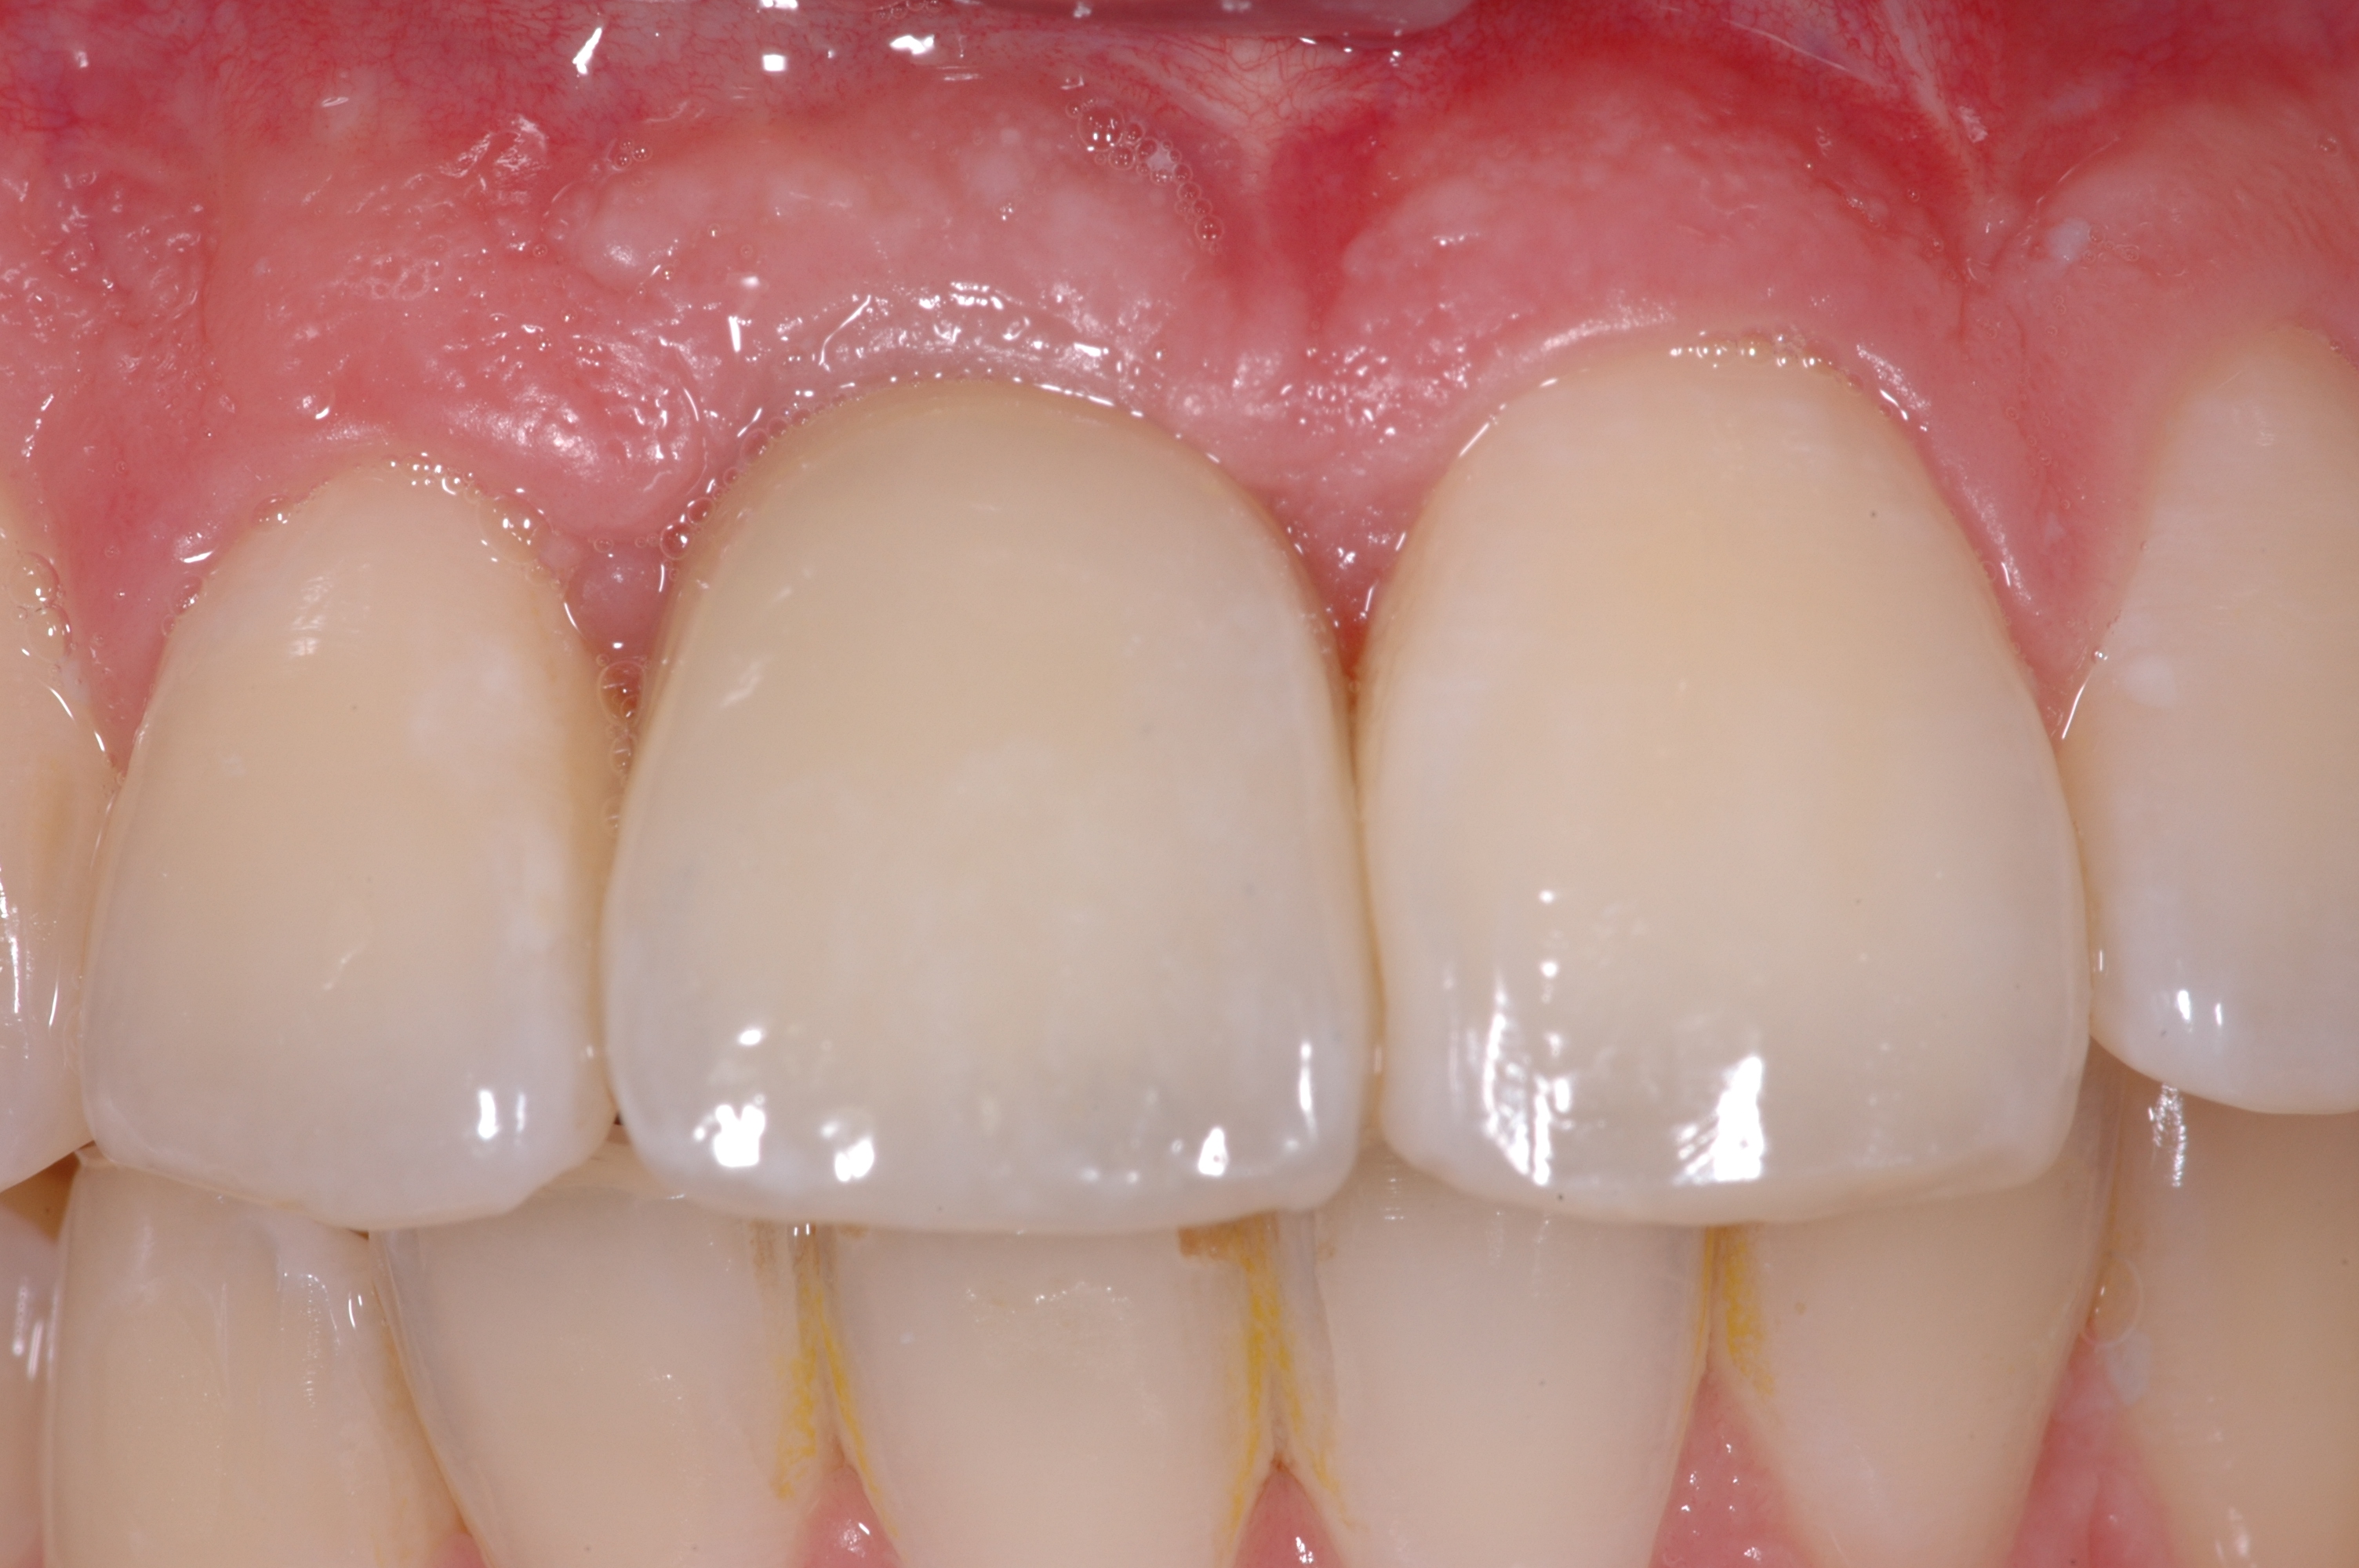

Cette racine artificielle permet de fixer une nouvelle couronne restaurant une nouvelle dent. Plusieurs implants peuvent porter plusieurs dents ou un bridge, jusqu’à la restauration d’une arcade complète. Les implants permettent également de stabiliser une prothèse amovible.

L‘implant permet d‘éviter de préparer les dents voisines de la dent perdue en vue de placer un bridge.

L‘implant permet d‘éviter une perte osseuse supplémentaire, suivant inévitablement toute extraction dentaire, par stimulation osseuse.

L‘implant permet de stabiliser une prothèse inconfortable, d‘améliorer la mastication, de soutenir les structures oro-faciales.